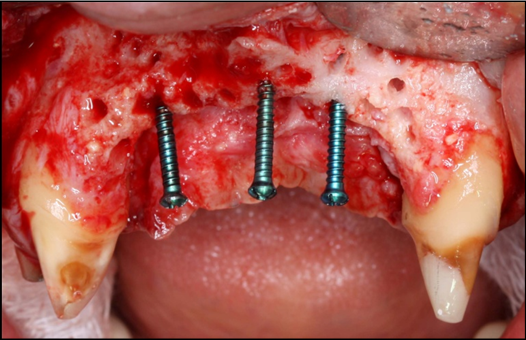

The surgical procedure was done under intravenous sedation using Fentanyl and Versed. Local anesthetic was used and a supra-crestal horizontal incision made on the palatal aspect of the anterior maxilla. A mucoperiosteal flaps were elevated, exposing a severely resorbed ridge of the pre-maxilla (Figure 2). Decortication was conducted with a round carbide bur in order to perforated the cortical aspect of the bone and expose the cancellous bone, to increase vascularity to the recipient site. Three screws were fixed parallel to the adjacent teeth, serving as “tent pole”. The screws had 14 mm length and approximately 6-8 mm of the tenting screws were exposed to the oral cavity (Figure 3). An absorbable collagen sponge (ACS) carrier/matrix was embedded with 12 mg of rhBMP-2 at 1.5 mg/mL (Infuse® Medtronic Sofamor Danek, Memphis, TN, USA) and allowed to absorb for approximately 20 min. The rhBMP-2/ACS was cut into strips, half of the strips were added to the natural bone mineral component derived from bovine bone (Geistlich Bio-Oss® granules small - 0.25 to 1 mm, Geistlich Pharma, Germany). Initially, some strips of rhBMP-2/ACS were placed over the buccal aspect of the residual alveolar ridge of the pre-maxilla, followed by strips mixed with bovine bone (Figure 4). The three screws were fully covered by rhBMP-2/ACS strips. Finally, a titanium mesh was adapted over the entire rhBMP-2/ACS graft and fixed with 2 monocortical screws, one on the buccal aspect and one on the palatal aspect of the ridge, respecting a 2 mm distance from the mesh to the adjacent teeth (Figure 5). Extensive undermining incision was conducted on the apical aspect of the buccal flap in order to achieve primary closure.

Figure 4.Occlusal view of the pre-maxilla after placement of strips of the rhBMP-2/ACS added to the natural bone mineral component derived from bovine bone.

Figure 5.Perspective view of the pre-maxilla showing a titanium mesh adapted over the entire rhBMP-2/ACS graft and fixed with 2monocortical screws, one on thebuccalaspect and oneon the palatal aspect of the ridge, respecting a 2 mm distance form the mesh to the adjacent teeth